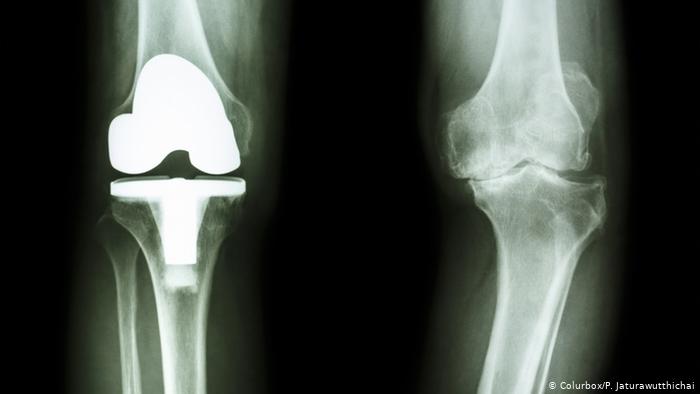

- يقوم الطبيب بإجراء شق في الركبة للوصول إلى المفصل المتضرر، بعد ذلك يبدأ الطبيب في إزالة الأنسجة والأربطة المتضررة ثم يبدأ في استبدال المفصل التالف بآخر صناعي.

- بعد ذلك بقوم الطبيب في تثبيت المفصل الجديد.

تبلغ نسبة نجاح عملية تغيير مفصل الركبة ما بين 90 إلى 95% كما يشترط أن تستعين بجراح ذو خبرة حتى تضمن أن تحصل على النتيجة المرجوة، كما يلعب عمر المريض عامل مهم في تحديد نسبة نجاح العملية.

كم يستغرق الشفاء من عملية تبديل مفصل الركبة؟

تستغرق مدة التعافي الكامل من عملية تبديل مفصل الركبة ما بين 3 إلى 6 أشهر ويقوم المريض في هذه المرحلة بالعديد من التمارين التي تساعده على العودة لممارسة أنشطة حياته بشكل طبيعي.

وتمر مرحلة التعافي بعدة مراحل قد تستمر لسنة كاملة حتى يعود الشخص لحياته ويستعيد صحته بشكل كامل.